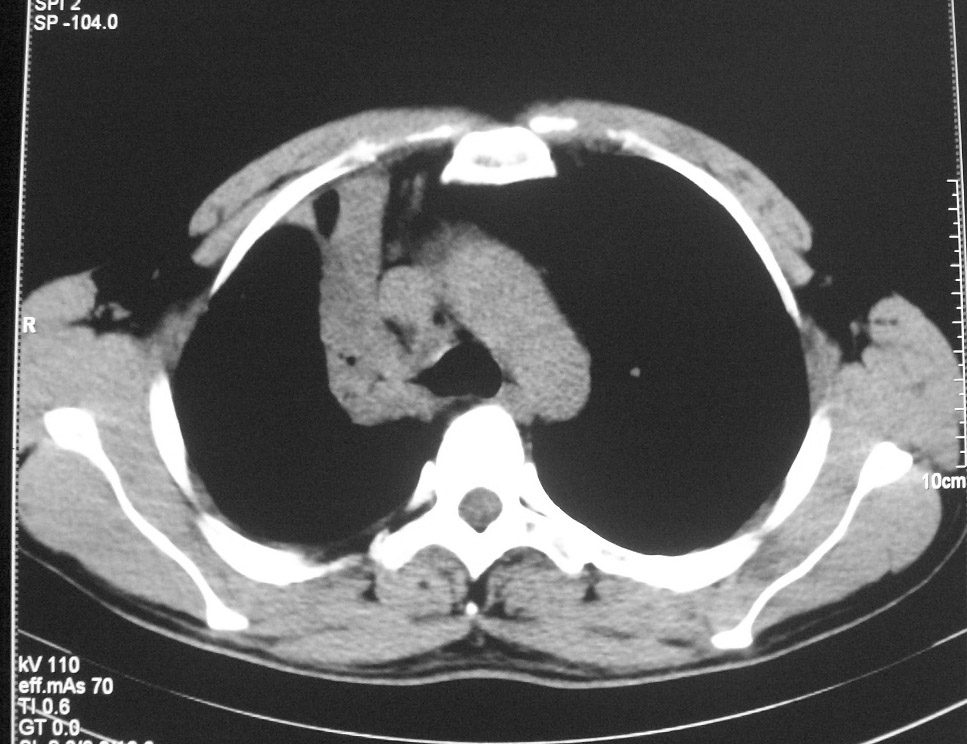

标题: CT5485:[原创]肺部占位请讨论

右上肺ca并肺不张,纵隔淋巴结转移

右肺上叶中央型肺癌并上叶肺不张、纵隔淋巴结肿大

右上叶支气管后壁明显增厚,支持右肺上叶中央型肺癌伴右上叶肺不张、纵隔淋巴结肿大。

右上叶支气管后壁明显增厚,支持右肺上叶中央型肺癌伴右上叶肺不张、纵隔淋巴结肿大。建议支气管镜检查。

右上叶支气管开口变窄,纵隔见肿大的淋巴结。支持右上叶中心型肺癌并右上叶不张纵隔淋巴结肿大。